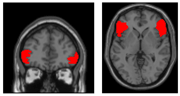

背側前帯状皮質 大脳半球内側面の前方部に位置する襟のような形をした領域で、競合の検出や解消、コストの計算、共感、情動など多くの重要な機能に関与している(右図の赤い部分)。 元の記事へ